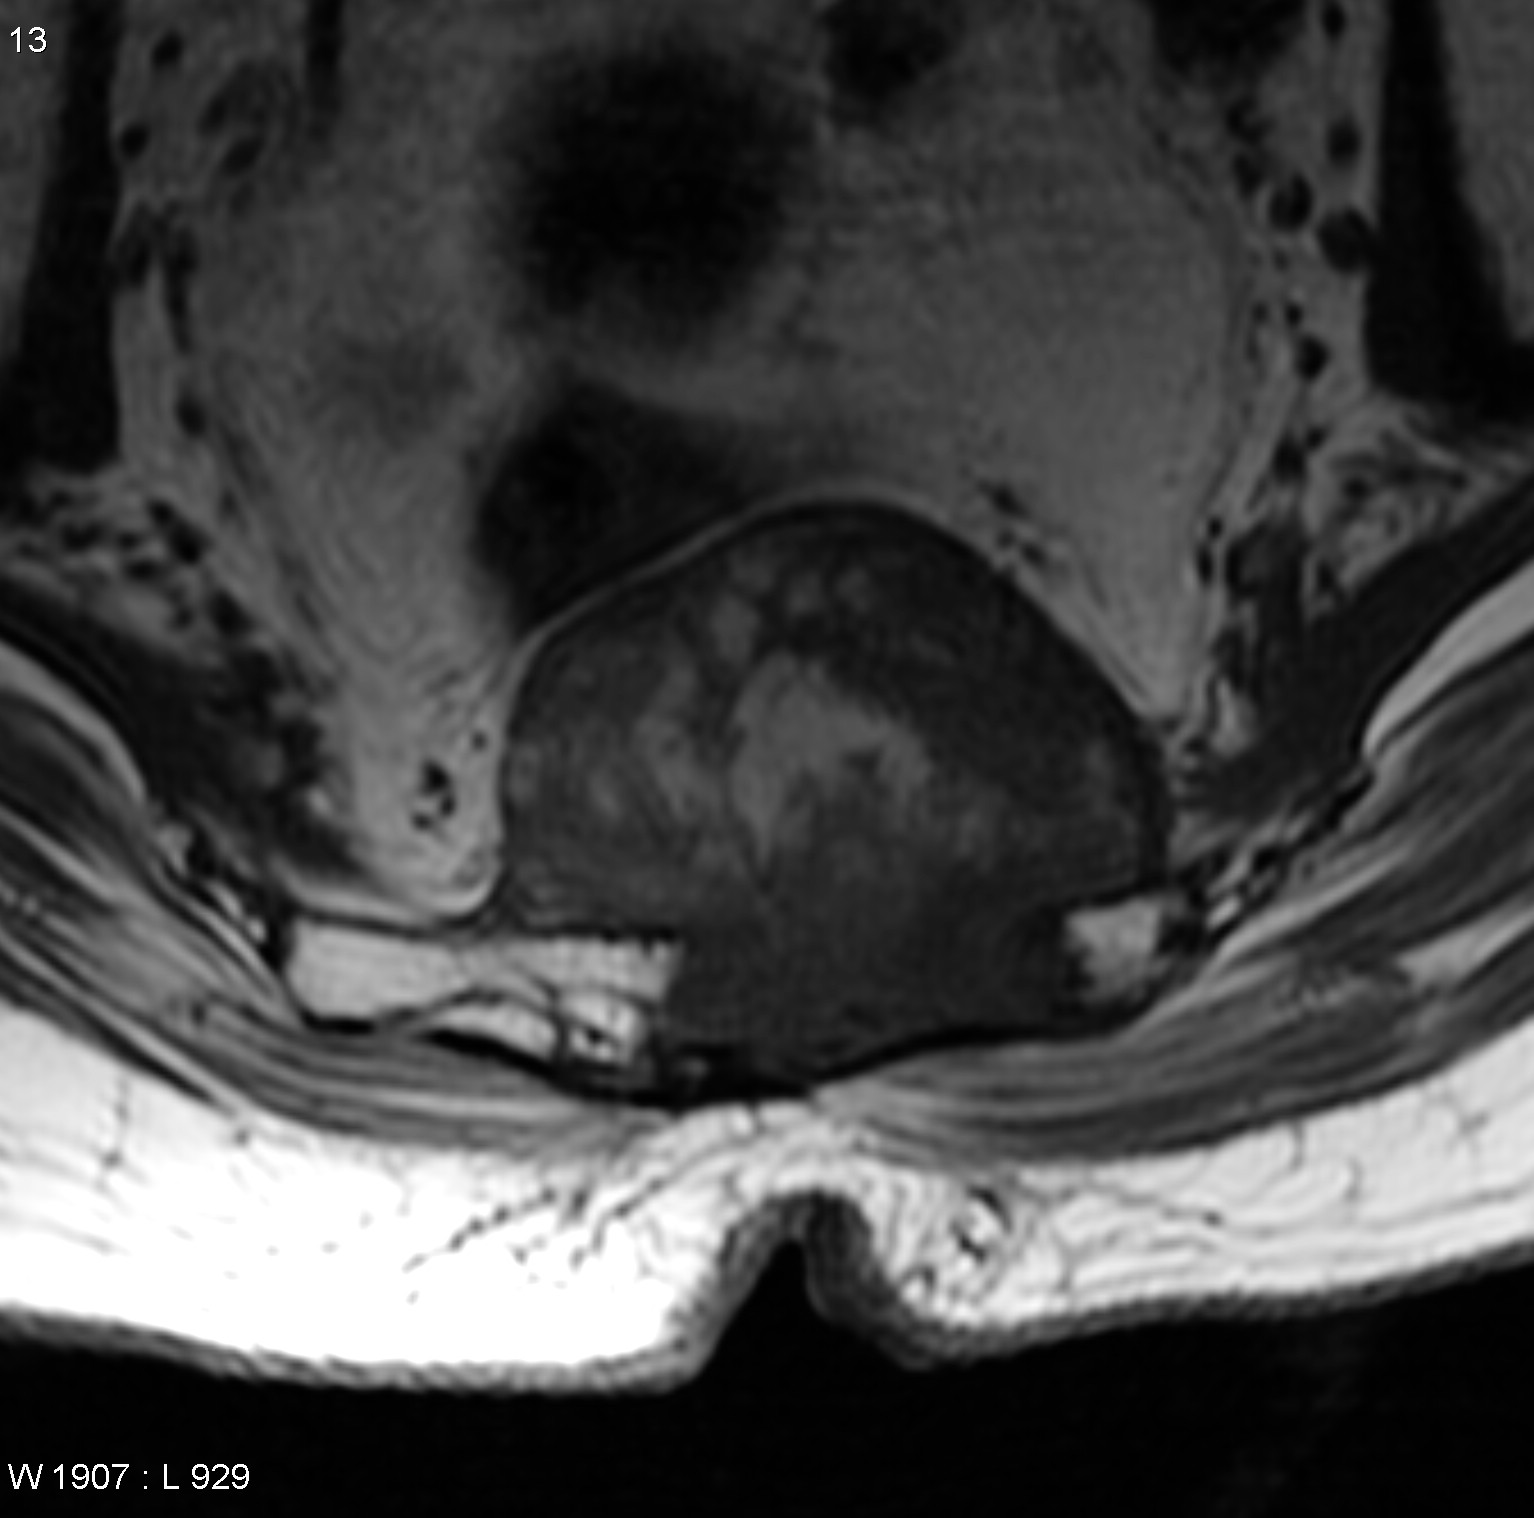

一名37岁的妇女因颈部疼痛和下颅神经功能障碍(声音嘶哑和吞咽困难)被咨询至我科。她先前被诊断出患有(CCJ) 颅颈交界处脊索瘤 ,并且先前在另一家医院进行了两次手术切除尝试...

法国一位37岁的女士因头痛、视力下降严重,到医院检查,被诊断出颅颈交界处(CCJ) 脊索瘤 。随后在一家比较医院治疗,该院采取了乙状窦后入路手术切除,但不久后,便再次复...